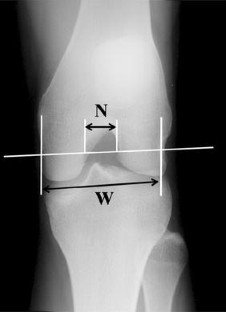

This was a comparative cohort study on 50 subjects of which 25 patients with sport trauma-associated bilateral ACL injuries, 30 with unilateral ACL injuries, and 20 healthy subjects. The notch width index (NWI) was measured as the ratio of the width of the intercondylar notch to the femoral condylar width on radiography and the MRI slice containing the region near the ACL attachment site on the femoral side (NWI-A) and on the following posterior slice (NWI-P).